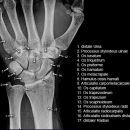

Hand / Handgelenk

Scaphoid-Quartett

Indikation

Dringender Verdacht auf Scaphoidfraktur (2) bei zweifelhaften Befund in den Standardprojektionen.Notwendigkeit fraglich, da bei klinischen Verdacht und zweifelhaften Röntgenbefund in den Standardaufnahmen des Handgelenks ohnehin die Ruhigstellung indiziert ist, so dass sich eine weiterführende Diagnostik zunächst erübrigt. Ist auch die Kontrolluntersuchung nicht eindeutig, so sind CT oder Szintigraphie in ihrer Aussage zuverlässiger als die Spezialprojektionen.

Scaphoidfrakturen: 70% der Frakturen der Handwurzel sind Scaphoidfrakturen. 2/3 sind im mittleren Drittel. Meist Querfrakturen.

Dehizenz > 1mm -> instabil -> Gefahr Pseudarthrose.

Cave: Begleitverletzungen: Proc. syloideus radii, Lunatum, Capitatum, SL-Dissoziation, perilunäre Dissoziaton, DeQuervain Luxationsfraktur.